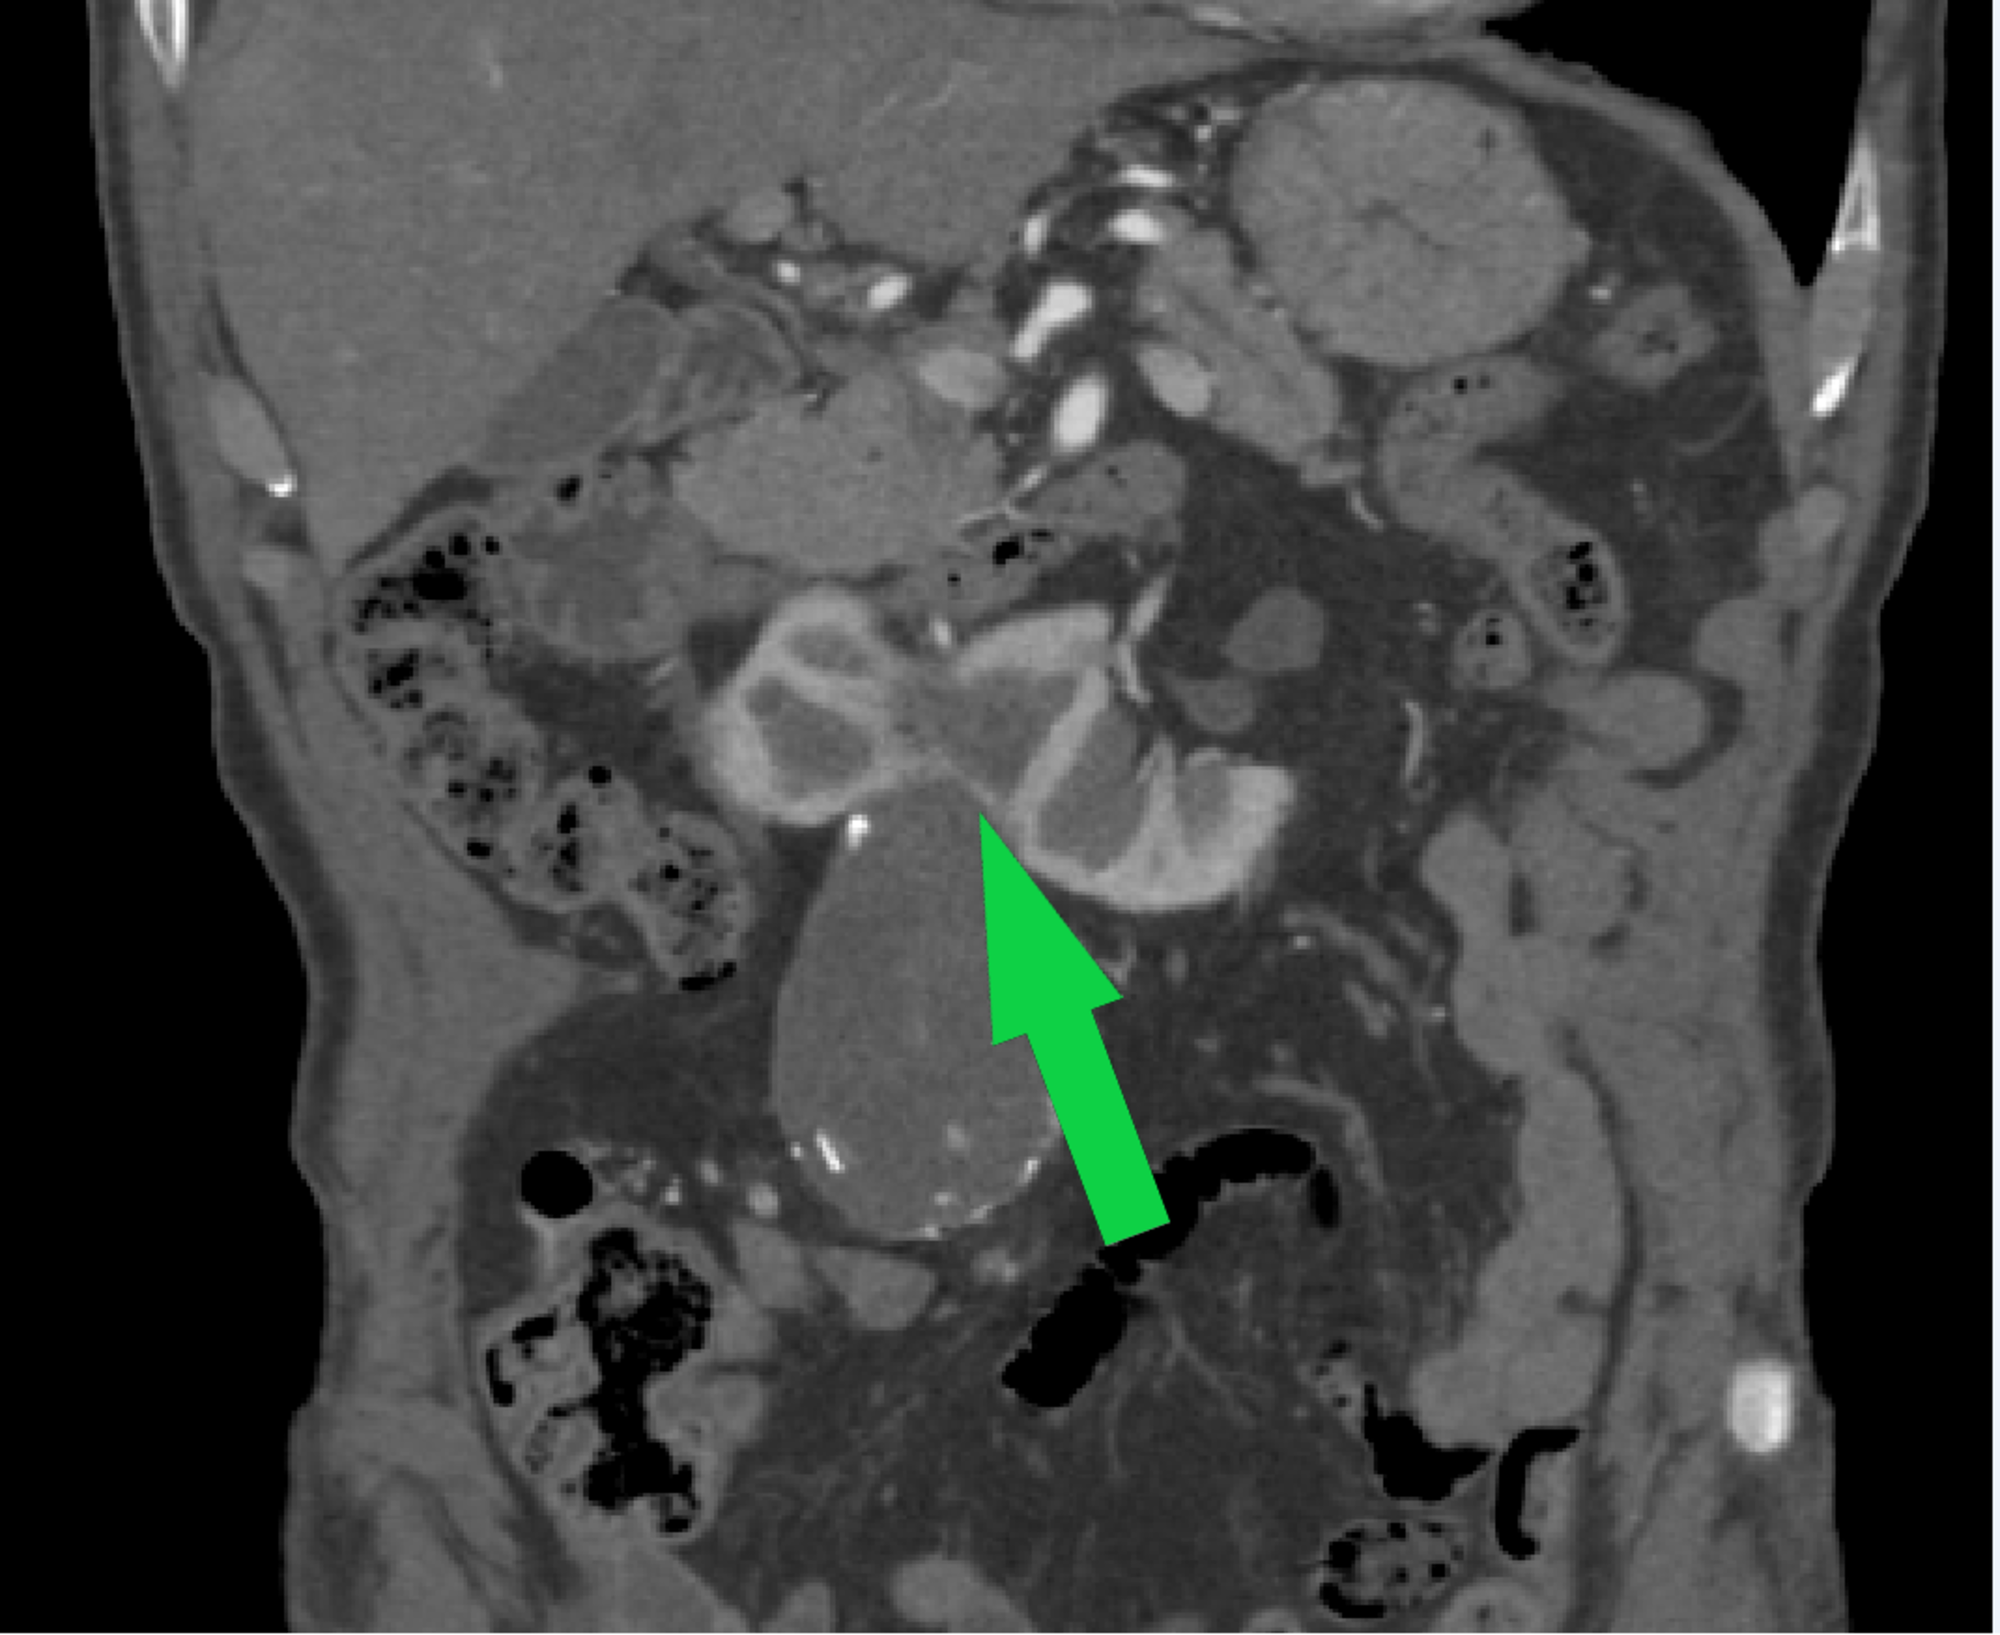

EVAR Approach for Abdominal Aortic Aneurysm with Horseshoe Kidney A Horseshoe Kidney Aaa Horseshoe kidney (hsk) is a rare congenital fusion defect and is uncommonly associated with abdominal aortic aneurysm. Horseshoe kidney (hsk), referring to the abnormal fusion of the lower renal poles, represents one of the most common renal. Ten patients with abdominal aortic aneurysms (aaas) and horseshoe kidney were treated with endovascular aneurysm repair. A systematic review of all patients that. Horseshoe Kidney Aaa.

Horseshoe kidney classification system based on the vasculature Horseshoe Kidney Aaa A systematic review of all patients that have been reported in the literature with abdominal aortic aneurysm (aaa) concomitant. Horseshoe kidney (hsk) is a rare congenital fusion defect and is uncommonly associated with abdominal aortic aneurysm. Coexistence of horseshoe kidney and abdominal aortic aneurysm (aaa) is a rare entity that presents a technical challenge to vascular. Horseshoe kidney (hsk), referring. Horseshoe Kidney Aaa.

Horseshoe kidney and AAA, with the inferior vena cava (marked by blue Horseshoe Kidney Aaa Coexistence of horseshoe kidney and abdominal aortic aneurysm (aaa) is a rare entity that presents a technical challenge to vascular. Horseshoe kidney (hsk) is a rare congenital fusion defect and is uncommonly associated with abdominal aortic aneurysm (aaa). A systematic review of all patients that have been reported in the literature with abdominal aortic aneurysm (aaa) concomitant. Horseshoe kidney (hsk). Horseshoe Kidney Aaa.